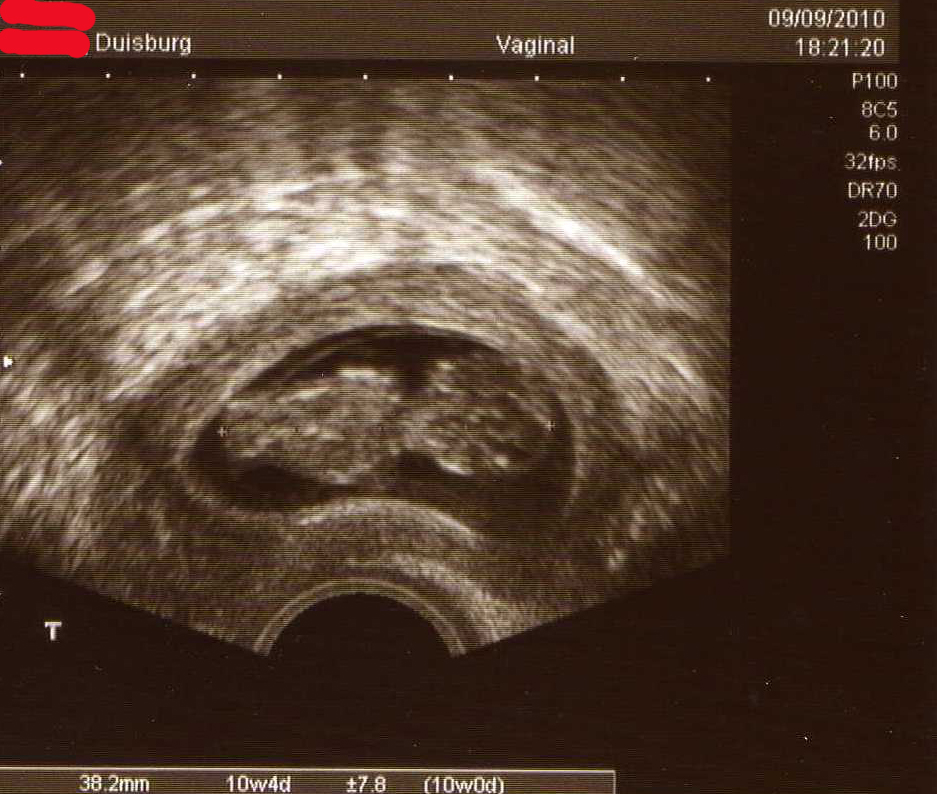

nur kurz: alles bestens, alles zeitgemäß, wir haben den Herzschlag auch heute hören können, Arme Beine alles dran.

Baby002.jpg

oh schööön.. ich hab schon die ganze Zeit gewartet.. soo ein kleines Menschlein.. mensch Muggelchen.. wie toll *freu freu freu

Muggelchen Tolles Bild! Herzlichen Glückwunsch! War bestimmt ein irres Gefühl, oder?

@Muggelchen, was für eine Figur eurer Krümmel macht! :D

Muggelchen: Ach wie schön das ist!!! Alles alles gute!!! *dd* *dd* *dd*